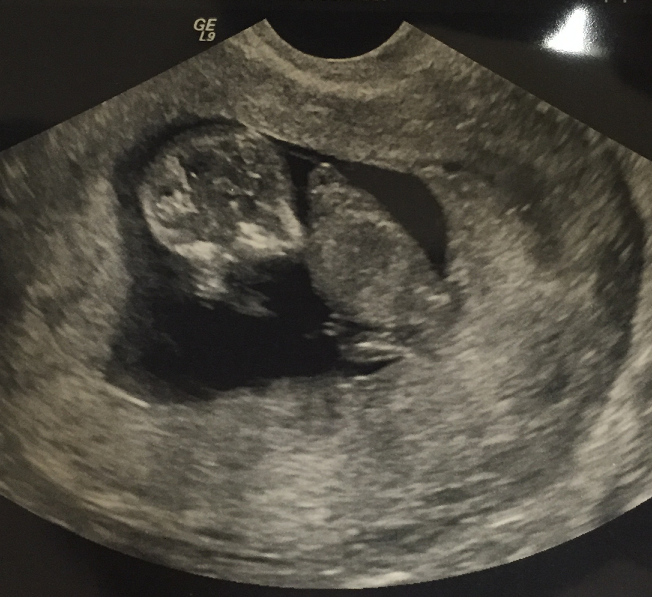

Three weeks ago, baby was measuring a day behind... I'm 11 weeks along today, but baby is now measuring 12 weeks. It was so amazing to watch the little one moving around, waving its arms, and we even got a picture when it was playing with its feet!

We had our second ultrasound last week when I was 11+3. Still measuring a bit bigger, she said I looked about 12 weeks during the scan. Everything looks healthy! Look at that little nose and lips!!!! So in love.